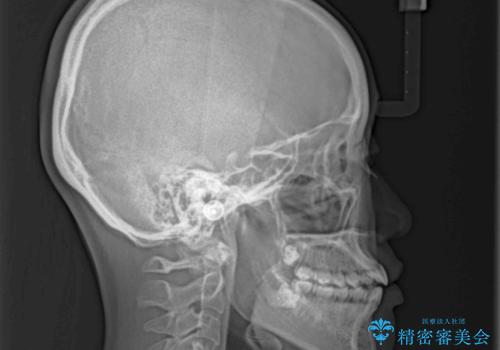

上下の奥歯を圧下させるようにすることで、前歯を接触させるように計画しました。

隙間に舌が入り込むことが話しにくさに繋がっていたため、舌の筋肉のトレーニングも並行して行い、話しにくさの改善と後戻りの抑制を図りました。